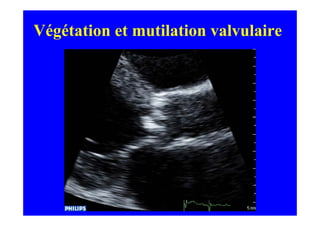

IAo par endocardite

Végétation et mutilation valvulaire